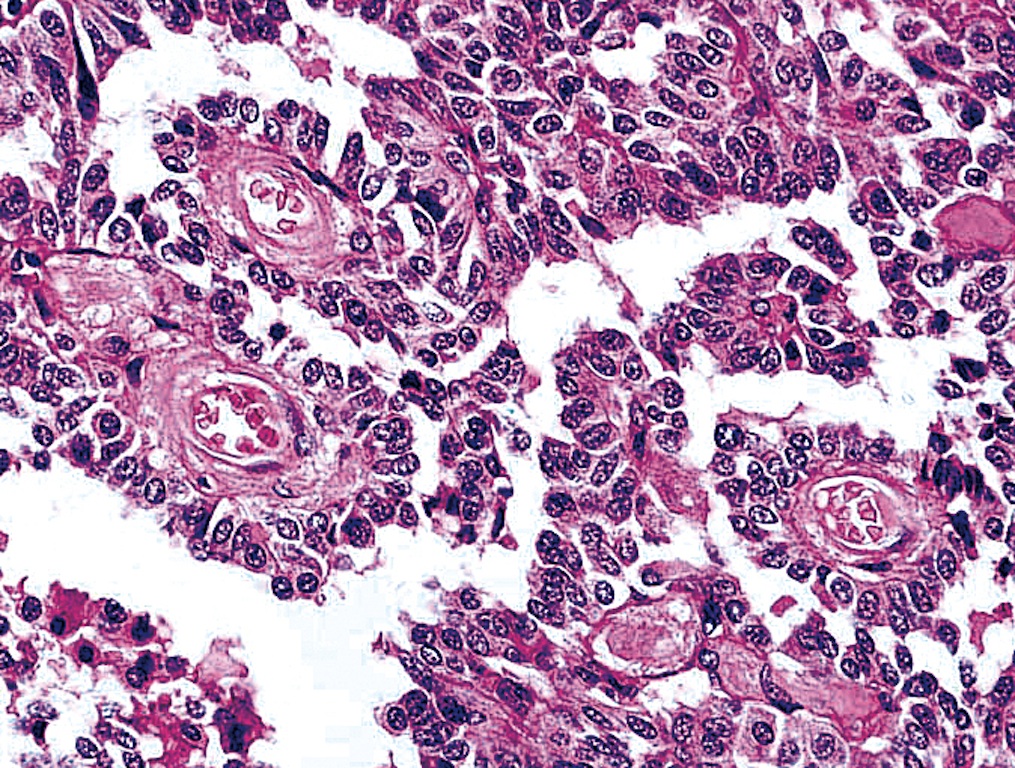

Microscopic (histologic) description

- Wide variety of morphology, can mimic any other thyroid malignancy

- Round, plasmacytoid, polygonal or spindle cells in nests, cords or follicles; often mixtures of these cells

- Round nuclei with finely stippled to coarsely clumped chromatin and indistinct nucleoli, occasional nuclear pseudoinclusion

- Eosinophilic to amphophilic granular cytoplasm due to secretory granules

- Generally low mitotic figures

- Stroma has amyloid deposits from calcitonin, prominent vascularity with glomeruloid configuration or long cords of vessels (Am J Surg Pathol 1995;19:642), coarse calcifications, occasional psammoma-like bodies

Microscopic (histologic) images

Contributed by Shuanzeng Wei, M.D., Ph.D., Joseph Christopher Castillo, M.D. and Mark R. Wick, M.D.

AFIP images

Images hosted on other servers: